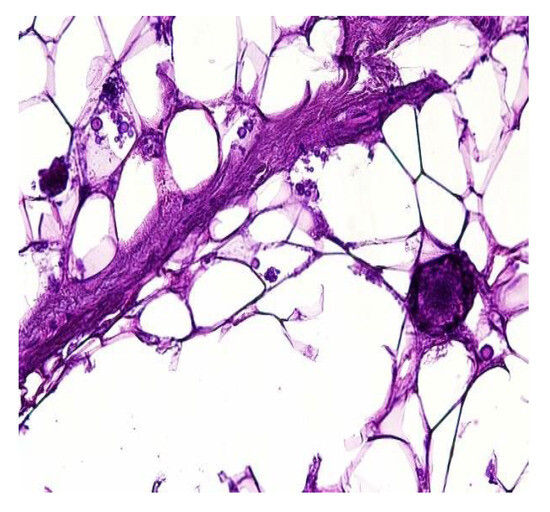

In both of the described cases, optical microscopy revealed lamellar fibrosis, deposits of fibrin on the surface of the peritoneum (Figure 3 and Figure 4) and dystrophic calcifications in the peritoneum (Figure 5 and Figure 6).

Figure 3. Lamellar fibrosis, condensed fibrin on the surface of the peritoneum and decreased cellularity (hematoxylin and eosin staining, original magnification × 100).

Jcm 13 02921 g003

Figure 4. Lamellar fibrosis, condensed fibrin on the surface of the peritoneum and decreased cellularity (hematoxylin and eosin staining, original magnification × 100).